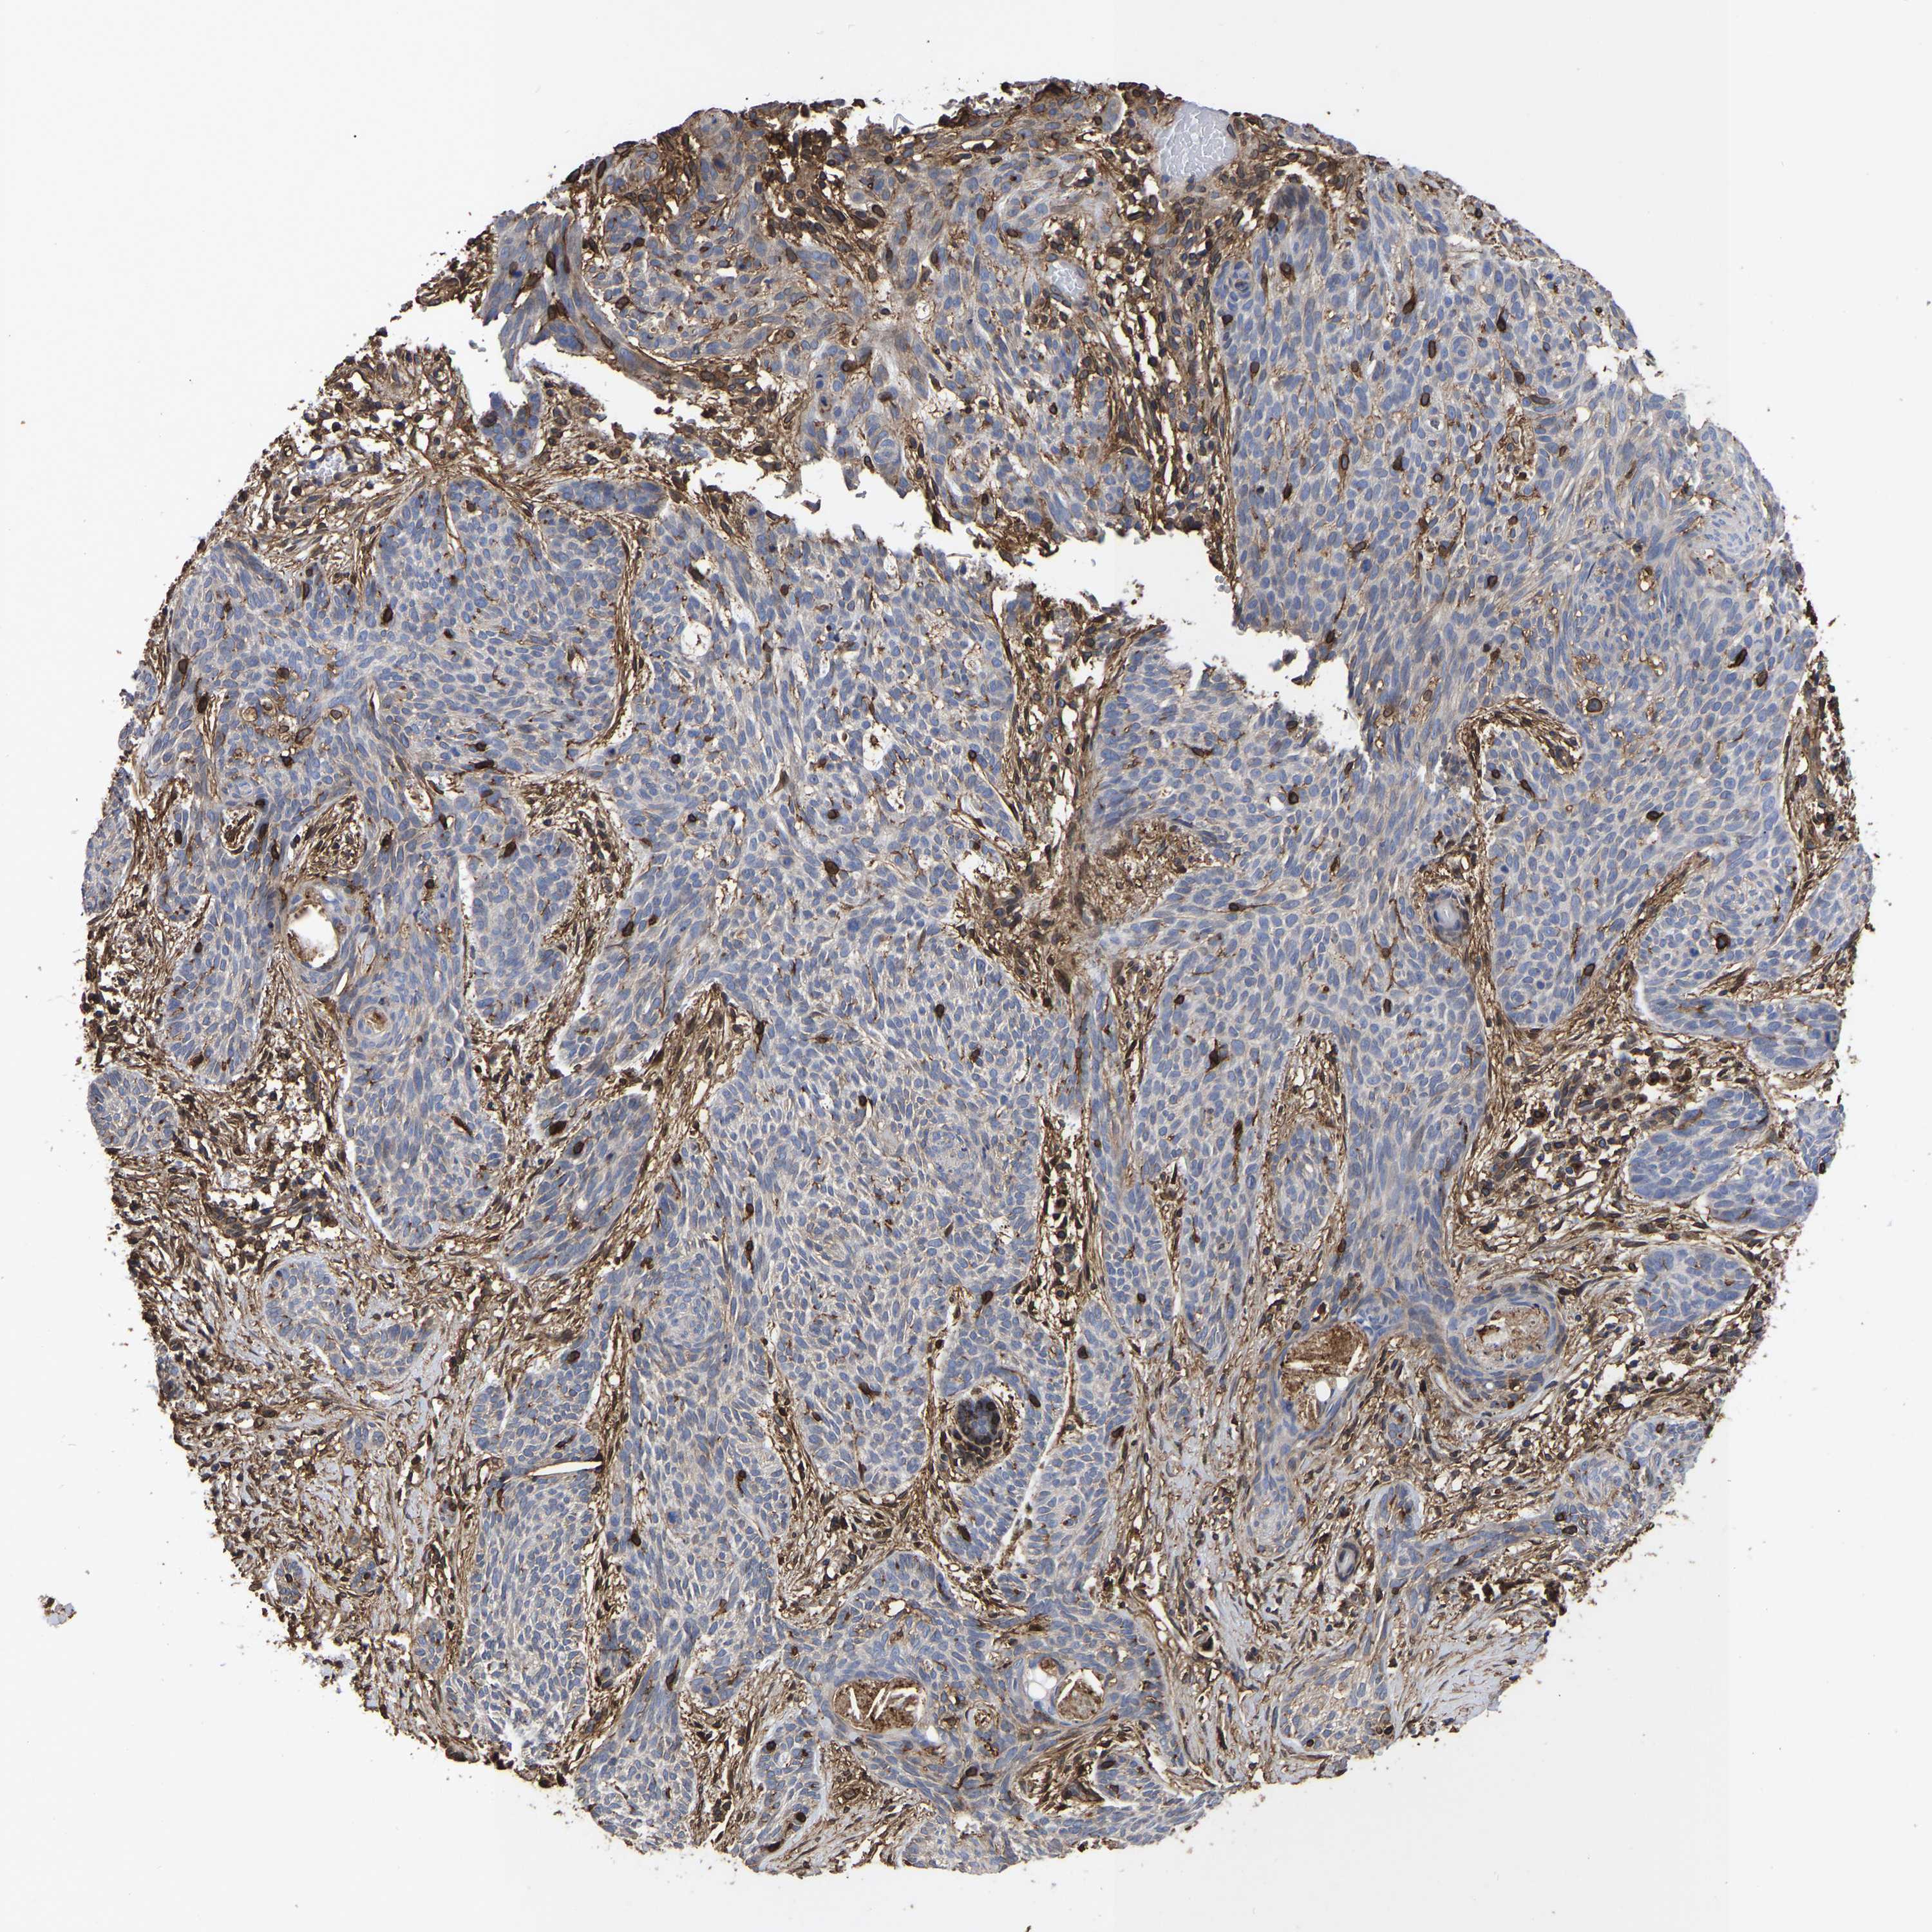

Basal cell and squamous cell cancer

SKIN CANCER - Protein expressioni

A mouse-over function shows sample information and annotation data. Click on an image to view it in a full screen mode. Samples can be filtered based on level of antibody staining by selecting one or several of the following categories: high, medium, low and not detected. The assay and annotation is described here.

Antibody stainingi

Antibody staining in the annotated cell types in the current human tissue is reported as not detected, low, medium, or high, based on conventional immunohistochemistry profiling in selected tissues. This score is based on the combination of the staining intensity and fraction of stained cells.

Each image is clickable and will lead to virtual microscopy that enables deeper exploration of all samples and also displays staining intensity scores, fraction scores and subcellular localization as well as patient and tissue information for each sample.

Antibody HPA018844

Staining

High

Intensity

Strong

Quantity

>75%

Location

Nuclear

Squamous cell carcinoma, NOS